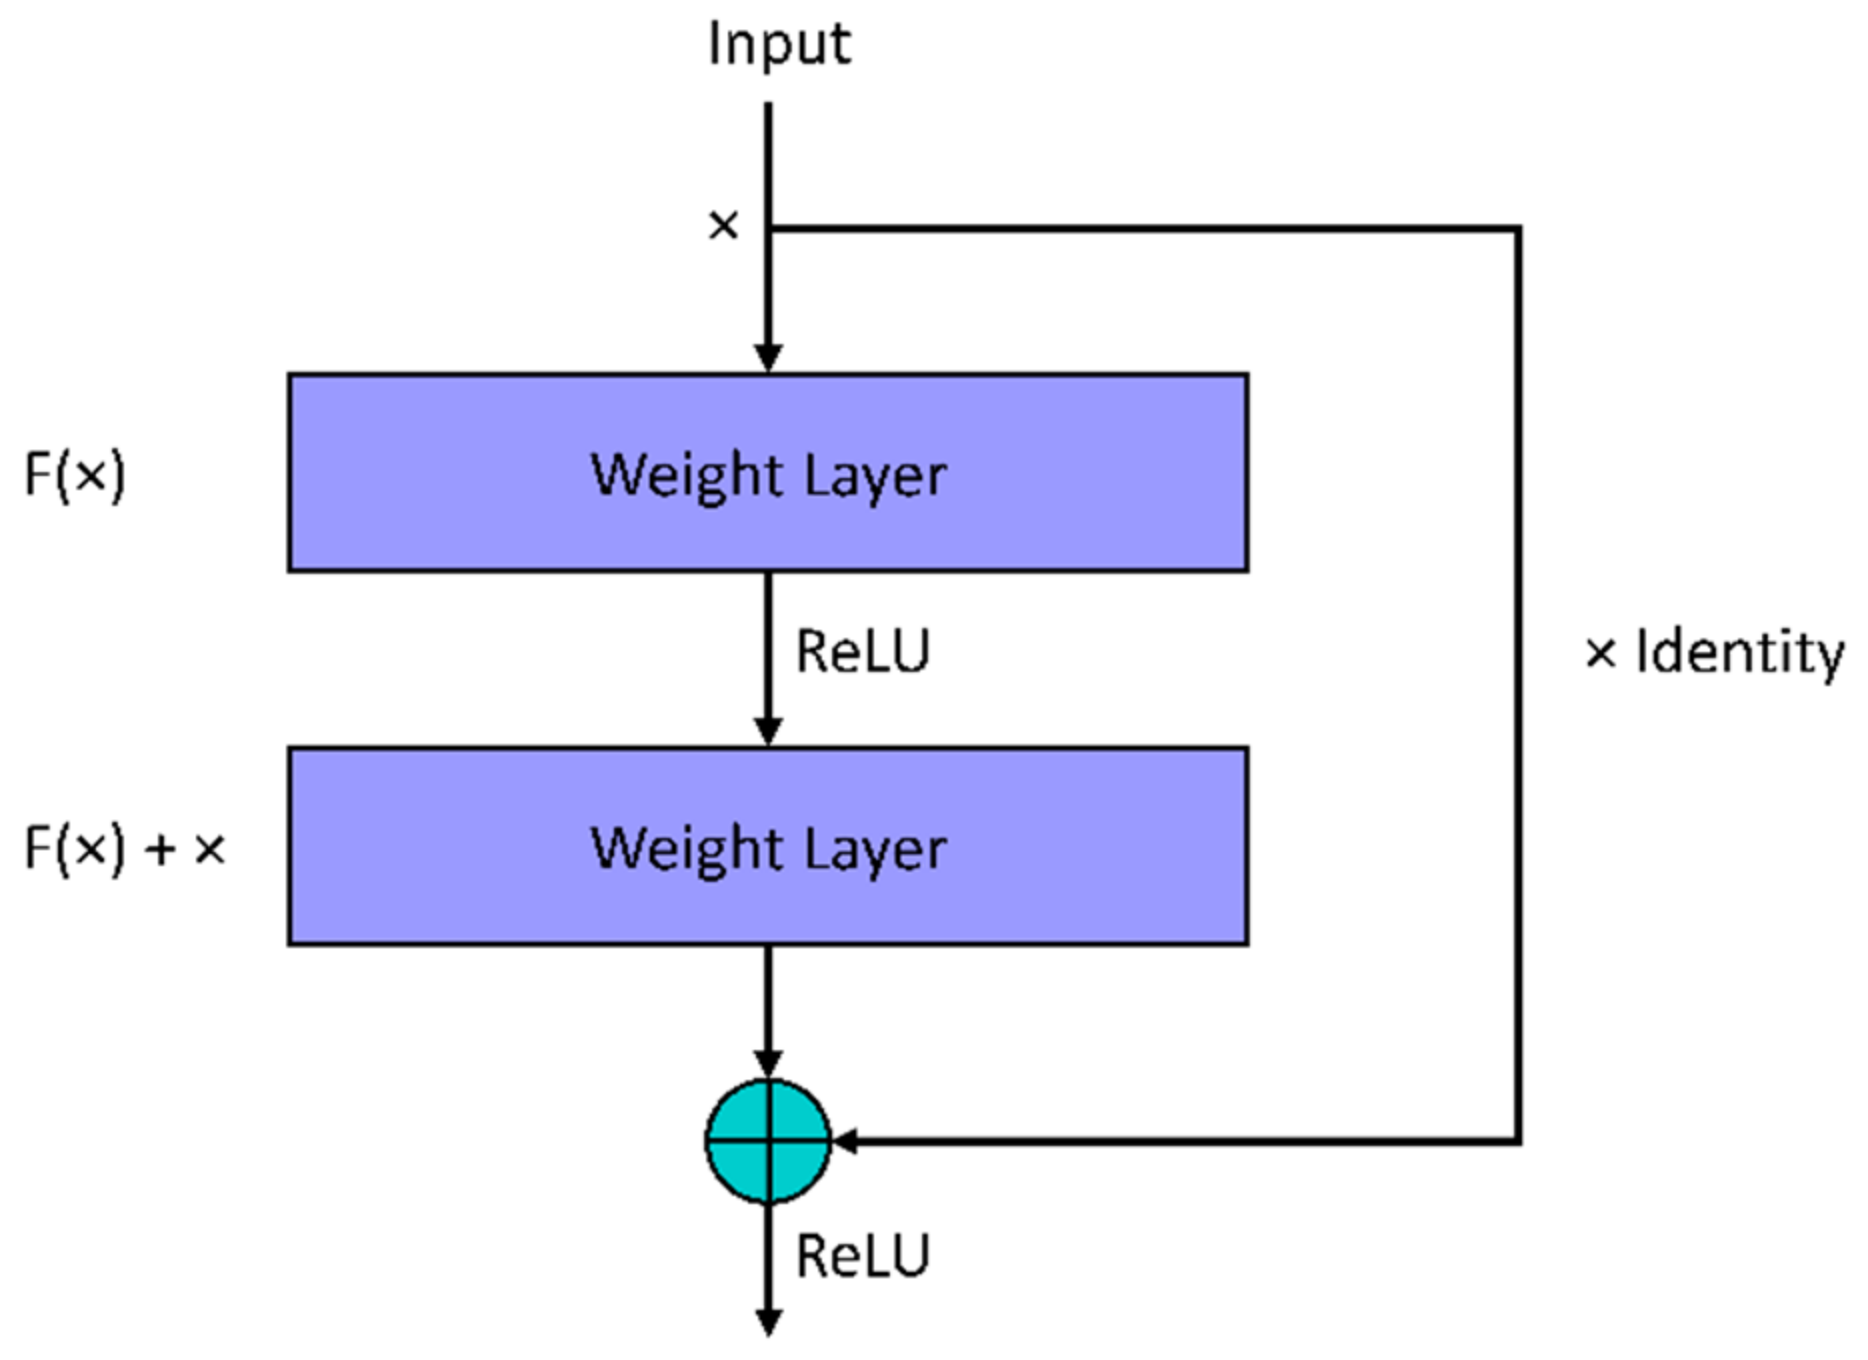

5.1.2. ResNet18